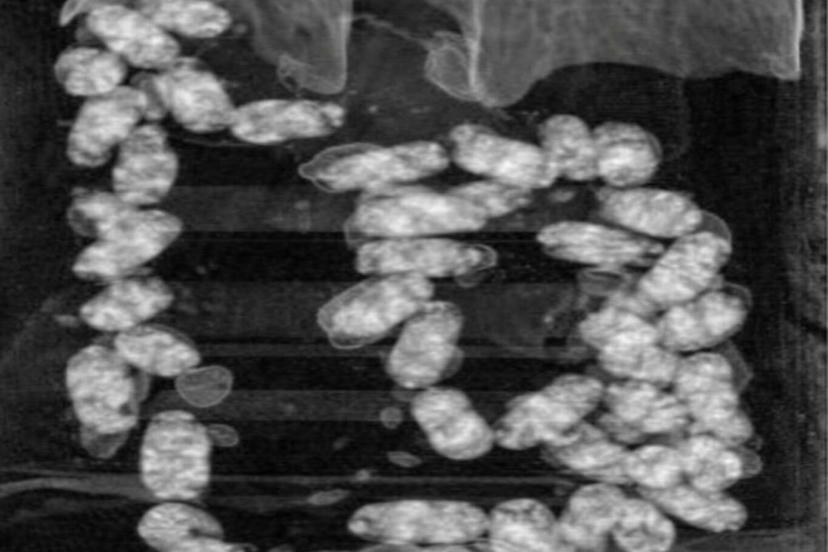

Şüpheliler üzerinde yapılan iç beden muayenesinde, 105 kapsül halinde yutulmuş vaziyette toplam 965 gram metamfetamin ele geçirildi.